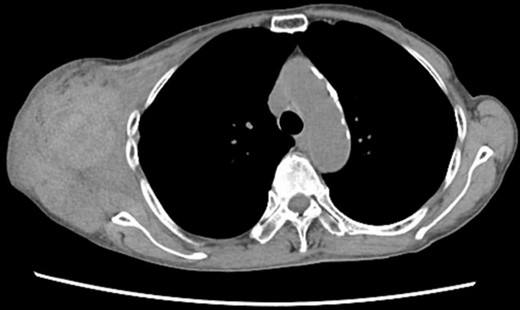

Four days later, the patient was hospitalized for rapidly worsening swelling and pain, and was readmitted with a diagnosis of rebleeding from the chest wall. Physical examination revealed a fist-sized subcutaneous mass on the right side of the chest, with severe pain. Laboratory data indicated anemia (Hb 7.8 g/dl) and no coagulation disorder: % prothrombin time (PT) 115.1%, prothrombin time-international normalized ratio (PT-INR) 0.93, and activated partial thromboplastin time 23.6 s. Computed tomography (CT) at the time of the first hemorrhage showed the hematoma on the right chest and anterior to the scapula (Fig. 2). Contrast-enhanced CT at the time of rebleeding showed an increase in hematoma and extravasation in the peripheral right lateral thoracic artery (Fig. 3). The patient was immediately treated with emergency angiography, which revealed active bleeding from a pseudoaneurysm of the right lateral thoracic artery. Thus, coil embolization was performed (Fig. 4). There were no TAE-related complications and the patient was discharged to home on the fifth hospital day. Oral clopidogrel was resumed and there has been no recurrence of bleeding.

Contrast-enhanced CT at the time of the second bleeding showed growth of the hematoma and extravasation of contrast agent in a branch of the right lateral thoracic artery.